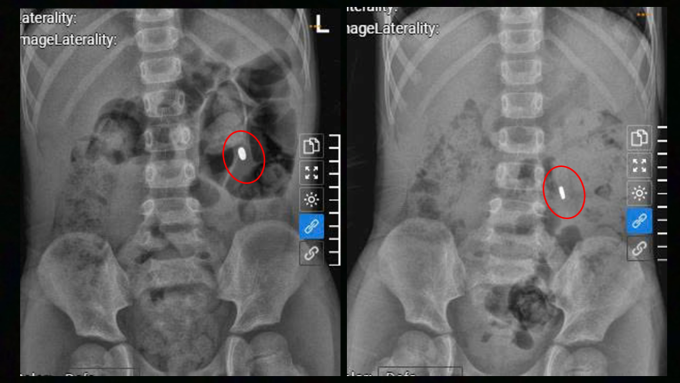

Bé Hoàng 4 tuổi vô tình nuốt đồ chơi có nam châm, ảnh chụp X-quang cho thấy dị vật vùng bụng trái.

ThS.BS.CKI Lê Thị Ngọc, khoa Nhi, Bệnh viện Đa khoa Tâm Anh TP HCM, cho biết xác định rõ số lượng nam châm rất quan trọng. Có hai tình huống có thể xảy ra với bé. Nếu dạ dày chỉ có một viên nam châm hoặc các viên dính thành một khối chặt, chúng có thể đi qua ruột và thải ra ngoài. Trường hợp các viên nam châm tách ra trôi đến những đoạn ruột khác nhau, chúng sẽ hút nhau xuyên qua thành ruột gây thiếu máu hoại tử, thủng ruột, viêm phúc mạc, đe dọa tính mạng.

Sau 4 ngày dùng thuốc, khối nam châm di chuyển xuống ruột non nhưng vẫn chưa thoát ra ngoài. Bác sĩ đổi liều thuốc, may mắn dị vật được đẩy ra ngoài, bé không phải phẫu thuật.